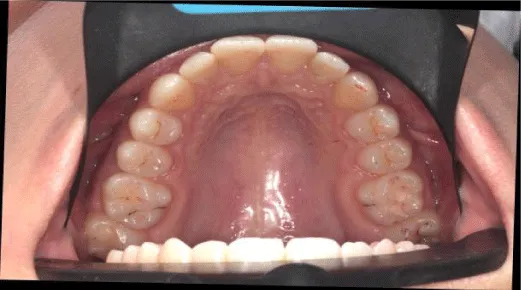

The procedure of the APTCA goes in the following sequence. After debanding patient is examined with T-scan III occlusal analysis procedure. The recording sequence is: centric occlusion, multi-bite, left lateral, and right lateral. Then occlusal foil (8 microns, Arti-Fol, Bausch, Germany) is placed between the teeth, patient is then asked to bite with the articulating paper in the mouth (Figure 2). Operator holds the articulating paper while the patient bites in his centric occlusion. These marks are then compared to the occlusal contacts viewed on the screen in patient`s centric occlusion recording (Figure 3). The highest forces on the teeth, which are seen on the screen exceeding the overall force level of 82%, have to be eliminated in the mouth. The force outliers on the screen are compared with paper marks on the patient`s teeth. The level of force does not usually correlate with the size of the occlusal mark. As described by Kerstein [20], small paper marks often tend to exhibit higher forces than larger marks.

The APTCA procedure is implemented by disclusion time reduction, which was first described by Kerstein [19,21], in the region on posterior teeth, both maxillary and mandibular. First patient is asked to bite on the sensor in his centric occlusion and then slightly move to canine edge-to-edge contact (Figure 4). The recording is then analyzed and the DT is checked (Figure 5). DT should not exceed 0,5 seconds [20]. Then the patient is asked to occlude his teeth in centric occlusion with green occlusal paper between his teeth. The excursive movement is afterwards performed with the use of red occlusal paper to mark excursive contacts. The method implements two colors of occlusal paper to mark centric occlusal contacts in green and excursive contacts in red. Red marks are easily recognizable and can be removed according to canine guidance scheme. The aim of APTCA is to achieve pure canine guidance in 0,5 seconds, eliminating posterior excursive contacts primarily. These contacts are consequently removed after each recording. The patient performs excursive movement with a sensor, paper marks are checked in the mouth, then excursive contacts removed on posterior teeth, and again the patient is asked to bite the sensor. It may take up to 8-10 cycles of repeated adjustment to achieve proper DT on the working side. The same procedure is done on the opposite side, when the patient performs lateral movement on the opposite working side.

Great emphasis is put on eliminating working contacts on the teeth posterior to ipsilateral canine. If teeth are already severely worn or sensitivity level is high, or canine is worn itself, canine`s restoration is essential to restore proper function and secure post treatment stability.